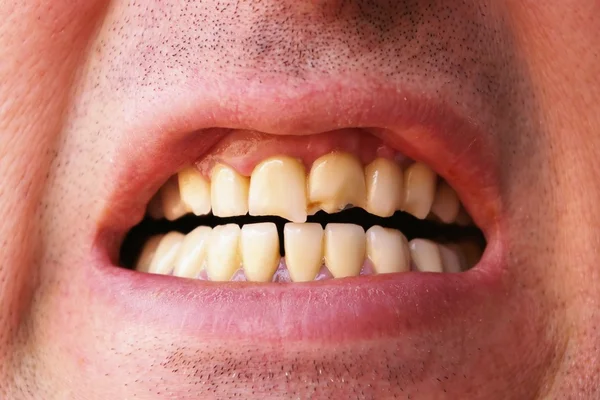

sp.depositphotos.com? Dientes Rotos Molesto, Abarrotamiento Foto De Archivo - Imagen De

sp.depositphotos.com? Dientes Rotos Molesto, Abarrotamiento Foto De Archivo - Imagen De

www.freepik.esDientes Rotos Masculino Dañado, Agrietado Diente Delantero Necesita

www.freepik.esDientes Rotos Masculino Dañado, Agrietado Diente Delantero Necesita

www.alamy.esRetrato De Un Hombre Con Los Dientes Rotos Imagen De Archivo - Imagen

www.alamy.esRetrato De Un Hombre Con Los Dientes Rotos Imagen De Archivo - Imagen